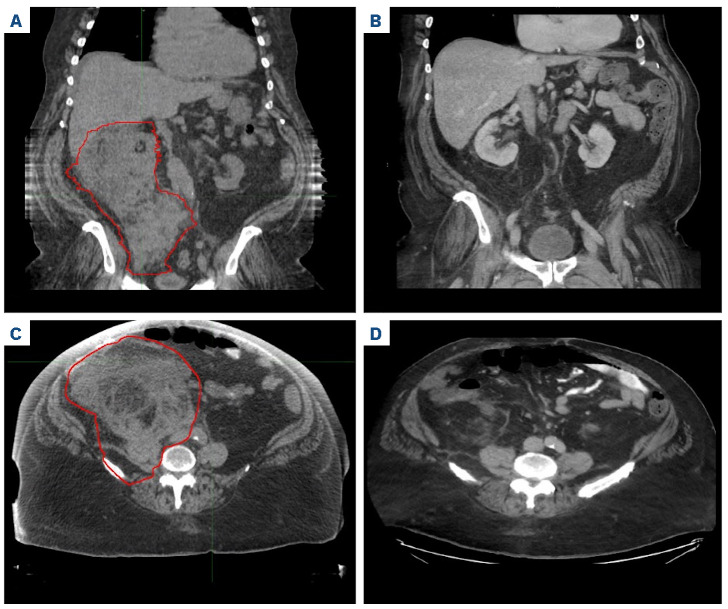

Radiation therapy to manage isolated relapse after chimeric antigen receptor T-cell therapy in multiple myeloma.